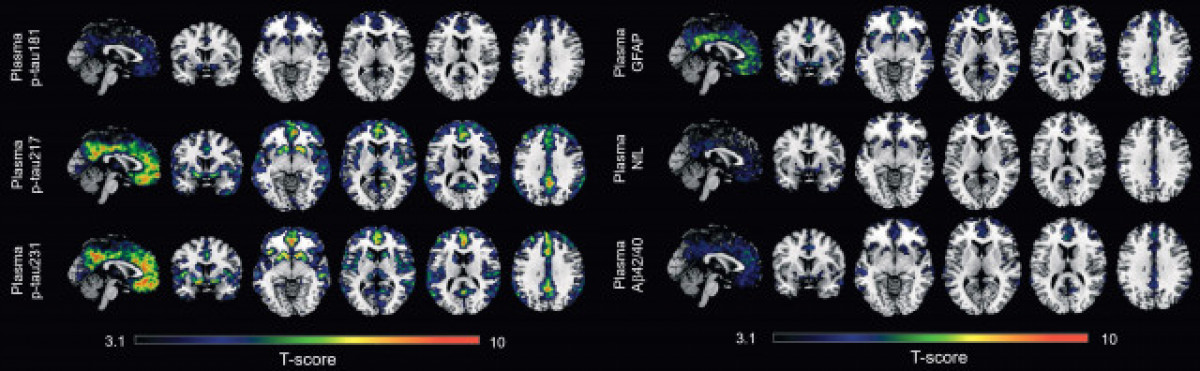

En col·laboració amb la Universitat de Göteborg, els investigadors han desenvolupat el nou biomarcador en sang p-tau231 i l'han comparat amb cinc biomarcadors més en sang --els p-tau181, p-tau217, Ab42/40, GFAP i NfL -- , prèviament estudiats a la fase simptomàtica de la malaltia d'Alzheimer.

Aquest és el primer estudi que investiga tots aquests biomarcadors a la fase preclínica de la malaltia d'Alzheimer, i els resultats mostren que p-tau231 i p-tau217 són els millors biomarcadors en sang per detectar els primers signes d'acumulació d'amiloide al cervell .

L'estudi indica que els biomarcadors en sang p-tau231 i p-tau217 van mostrar l'associació més forta amb la retenció d'amiloide a regions d'acumulació primerenca al cervell i es van associar amb augments longitudinals en la captació d'aquesta proteïna en individus sense patologia amiloide manifesta quan comença l'estudi.